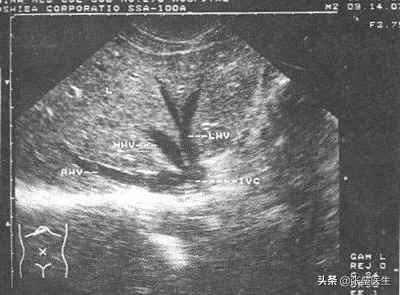

Le quatrième.Échographie du foieL'échographie est comme un "radar" qui peut nous aider à diagnostiquer s'il y a une anomalie dans la forme du foie, le degré d'endommagement du foie et s'il y a une lésion substantielle (foie gras, cirrhose, etc.) grâce à l'imagerie par ultrasons.

(1) Échographie du foie

- Le premier et le plus important est l'examen échographique du foie, qui est également l'examen médical le plus couramment utilisé dans la vie quotidienne et qui est largement plébiscité, notamment pour son excellent rapport coût-efficacité dû aux avantages d'un coût inférieur et d'une reconnaissance supérieure.L'échographie du foie permet de détecter clairement des maladies telles que les hémangiomes hépatiques, les kystes hépatiques et la stéatose hépatique, et de déterminer le stade et la gravité de la maladie sur la base des images. En outre, l'échographie du foie présente l'avantage d'être plus précise et plus sensible dans la détection des calculs de la vésicule biliaire, des calculs du canal biliaire intrahépatique et des calculs du canal biliaire commun.

2.B超

L'échographie est l'examen le plus rentable et le plus pratique pour contrôler votre foie. Qu'il s'agisse d'une stéatose hépatique, de kystes hépatiques, d'un hémangiome hépatique, d'un abcès hépatique, de calculs des voies biliaires intrahépatiques, d'une cirrhose ou d'un cancer du foie, l'échographie sera en mesure de les voir tous.

De nos jours, l'échographie du foie fait partie intégrante des examens médicaux proposés dans les hôpitaux. Les kystes hépatiques, les hémangiomes hépatiques et la stéatose hépatique sont les diagnostics les plus courants. La stéatose hépatique n'est pas un problème majeur, mais si elle entraîne des modifications de la fonction hépatique, elle doit être traitée. Les kystes hépatiques mesurent généralement plus de 5 cm et présentent des symptômes qui doivent être traités. Bien entendu, les kystes hépatiques de plus de 10 cm ne présentant aucun symptôme doivent être traités. L'hémangiome hépatique est également une maladie bénigne, et le traitement standard est similaire à celui des kystes hépatiques, qui dépend également de la taille et des symptômes.

La plus grande crainte de l'examen du foie est de trouver une masse de nature inconnue, ou une occupation, pour commencer. Cela signifie que l'échographie de la masse ne peut pas confirmer le diagnostic, il est possible qu'il s'agisse de quelque chose de malin et qu'il faille procéder à des examens complémentaires, tels que la tomodensitométrie et l'imagerie par résonance magnétique.

L'échographie est la méthode d'imagerie clinique du foie la plus couramment utilisée. Elle permet de déterminer si la morphologie du foie est anormale, s'il y a une cirrhose et son degré, s'il y a une stéatose ou des lésions occupant de l'espace dans le foie, s'il y a des anomalies dans le système biliaire intra- et extra-hépatique, s'il y a une anomalie dans l'hémodynamique hépatique, si la fonction de la vésicule biliaire est normale, etc. En règle générale, un échographiste expérimenté peut détecter des lésions d'une taille supérieure à 5 mm. Bien entendu, si les conditions économiques le permettent, il est également possible d'effectuer un scanner ou une IRM.

Le test de dépistage le plus couramment utilisé est l'échographie, qui utilise les ultrasons et l'imagerie informatique pour déterminer s'il y a des anomalies dans la morphologie du foie, l'étendue des lésions hépatiques et s'il y a des changements substantiels. Elle permet de diagnostiquer initialement une hépatite, une cirrhose, une stéatose hépatique, un cancer du foie et d'autres lésions. Lors de l'examen physique général, l'échographie hépatique peut servir de base, et un scanner ou une IRM peuvent être réalisés en cas de résultats suspects ou positifs.

Échographie du foie

1. le contenu de l'inspection :L'échographie en mode B permet d'observer le contour du foie, la paroi thoracique et abdominale et les échos parenchymateux ; les structures tubulaires et le trajet du parenchyme hépatique ; la statique hépatique et les veines portes, ainsi que les voies biliaires intrahépatiques et les artères hépatiques.

2. l'objectif de l'inspection :À l'aide des différentes données du rapport d'examen converties à partir de l'image échographique en mode B, le médecin peut déterminer si le foie est normal ou non, ou s'il y a une maladie du foie.

⑥L'échographie hépatique : cet examen n'est pas coûteux, et il n'y a ni radiation ni traumatisme, vous pouvez obtenir une compréhension générale des vaisseaux sanguins du foie et de leur distribution, du flux sanguin, du diamètre interne artériel et veineux, de la taille du foie, de l'écho, des canaux biliaires ne sont pas dilatés, de l'état péritonéal, il n'y a pas de kystes, il n'y a pas d'occupation, il n'y a pas de foie gras, la cirrhose peut être un examen très intuitif.